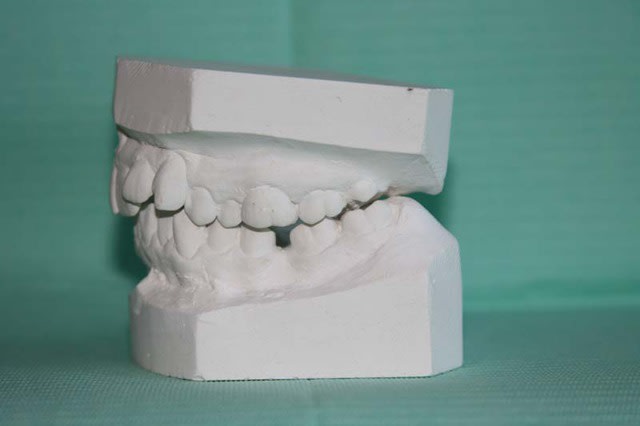

MOULAGES

Moulage 3 kvumyd - Eugenol

Moulage 1 vlrapq - Eugenol

Moulage 2 dllhb9 - Eugenol

Moulage 4 etnevt - Eugenol